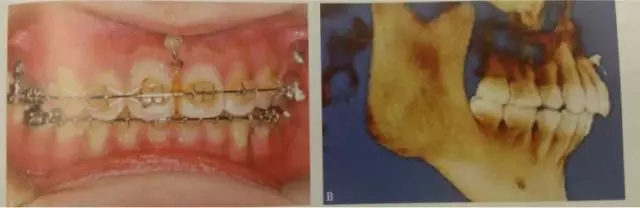

这是临床上最常见的应用方式,多用于需要强支抗内收前牙,常种植于第二前磨牙与第一磨牙、第一磨牙与第二磨牙之间,应根据X线片观察牙根间距离和邻近解剖结构确定具体部位,采用微种植体一方面可以获得绝对支抗以尽可能内收前牙,另一方面可整体内收6个前牙而不担心支抗问题,节省了治疗时间。